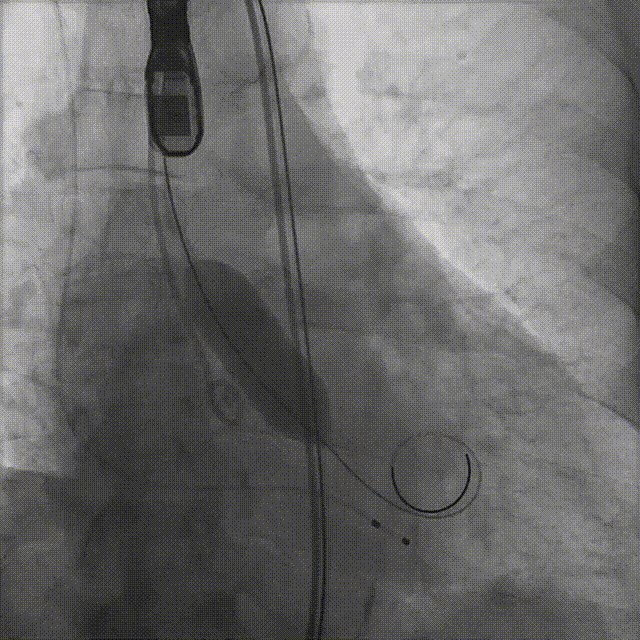

病例概览

患者病史 男性,74y, 因 “发现心脏瓣膜病 1 年,加重伴喘气半年” 入院。门诊检查显示主动脉瓣重度AS并伴轻-中度AR。患者基础疾病较多:胸腹主动脉多发穿透性溃疡、心功能III级等,手术指征明确,但风险极高。 术前CT LVOT- Annulus 倒梯形,对植入瓣膜有挤压位移风险,Annulus直径23.7mm,瓣叶增厚,钙化集中在无冠窦边缘。 左冠脉开口高度可,瓣叶不长、窦部空间较大,无冠脉风险;室间隔膜部较短,有一定PPI风险,心脏角度37.9°;心室较小,有一定循环崩溃风险,术前注意补液。 术前造影角度及入路:血管入路散在钙化、无迂曲;主动脉弓条件好、双侧股动脉直径大、右股穿刺点侧壁存在环形钙化 左右重合位:RAO 7° CAU 21° 右窦中心位:LAO2 1° CAU 1° 手术策略 20mm球囊预扩后植入AV26瓣膜,同时做好预防循环崩溃、传导阻滞的应急预案。 术中挑战 1)球囊预扩:20mm球囊预扩时无明显 “腰征”,但存在少量反流,提示瓣膜钙化与解剖结构对扩张的阻力不均 2)首次释放偏差:第一次定位释放时,瓣膜在 “开花” 过程中下滑约 3mm,工作位观察显示小弯侧瓣周漏较多(深度超过完全覆膜区),需二次调整。 3)二次精准定位:以猪尾导管为参照,将定位点调整至 “猪尾 - 2mm” 处,结合真实窦底深度(较深)重新释放,最终瓣膜位置稳定,瓣周漏显著减少。 术后即刻效果: 瓣膜形态良好,跨瓣压差从术前的 67mmHg 降至 6mmHg,且无明显瓣周漏,冠脉开口通畅; Commisural Alignment 术后即刻超声: Prostyle A®预装干瓣——助力临床最优化解决方案: √ 平衡的径向支撑力:特殊的解剖结构下位置形态良好,术后跨瓣压差大幅降低,血流动力学改善明显; √ 80%可回收设计:支持术中二次调整释放位置,保证精准释放; √ 平衡的收腰设计&Commissural Alignment设计: 为患者后期冠脉PCI保留了生命通道;